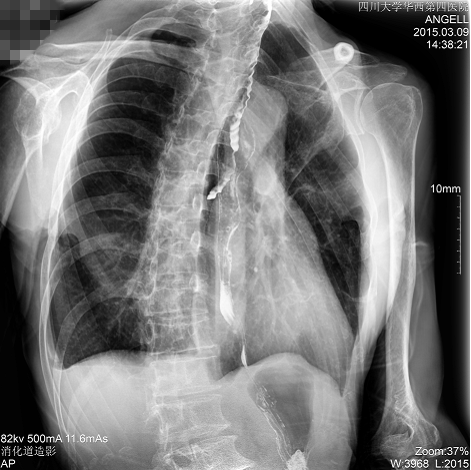

如下圖所示:該患者因吞咽時感到很難受,進食時也經(jīng)??人怨示歪t(yī)診斷。使用多功能dr為病人進行消化道造影診斷,要求他吞鋇后發(fā)現(xiàn),食道各段通過順利,形態(tài)規(guī)則,雙側(cè)梨狀窩不對稱左側(cè)稍淺,多次吞咽動作后,仍見鋇劑滯留,并見鋇劑進入氣管,屬于會厭征陽性。會厭功能紊亂,鋇劑進入了氣管。

圖為斜位:通過動態(tài)影像可以清楚看到鋇劑進入了支氣管道

通過多功能dr可以診斷該病人的癥狀為會厭功能紊亂,鋇劑進入到了氣管。而在動態(tài)透視下可以清晰的觀察到鋇劑從何處進入氣管,可清晰顯示食管粘膜結(jié)構(gòu)。使用多功能dr其獨特的視頻采集技術(shù),可實時保存視頻并能實現(xiàn)900萬像素實時點片,才能獲取這樣清晰的病灶點。而常規(guī)dr只能拍攝靜態(tài)片,且成像效果大打折扣,因此較難確診病灶。